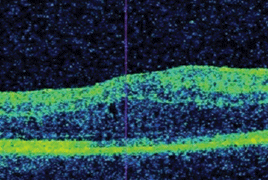

- Výsledky reoperací perzistující primární makulární díry

- Subjektívne zmeny vo videní u pacientov s diabetickým makulárnym edémom liečených ranibizumabom

- Postradiačná makulopatia u pacientov s malígnym melanómom corpus ciliare a chorioidey po stereotaktickej rádiochirurgii